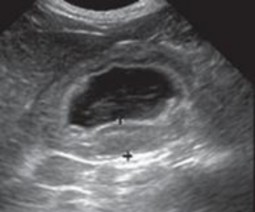

Hình 4.25. Hình ảnh siêu âm tử cung bị viêm của giống Poodle 5 tuổi

(mũi tên)

Siêu âm đóng vai trò quan trọng trong chẩn đoán bệnh viêm tử cung, các phát hiện siêu âm điển hình phù hợp với viêm tử cung bao gồm chứng to tử cung, thành tử cung dày lên, thay đổi tăng sinh nội mạc tử cung, sừng tử cung hình ống xoắn do chất lỏng gây ra, và giảm âm vang trong lòng tử cung chứa dịch. Siêu âm có thể phân biệt viêm tử cung với các mô mềm khác, khiến tử cung căng lên và là điều bắt buộc để đánh giá về sự hiện diện của tăng sản nội mạc tử cung và sự nguyên vẹn của nội mạc tử cung (Nyland & Mattoon, 2002; Wallace & Casal, 2018). Tương tự nghiên cứu Hagman (2018) khi sử dụng siêu âm để chẩn đoán bệnh viêm tử cung và tăng sản nội mạc tử cung, trên chó mắc tăng sản nội mạc tử cung quan sát thấy thành tử cung dày lên và có các cấu trúc nang không cản âm và không có dịch trong tử cung, trong khi đó với trường hợp chó vừa bị viêm tử cung và tăng sản nội mạc tử cung quan sát thấy thấy thành tử cung dày lên và có các cấu trúc nang không cản âm và quan sát dịch trong tử cung. Tương tự nghiên cứu Mattei & cs. (2018) khi thực hiện chẩn đoán trên một chó Labrador Retriever 7 tuổi chưa sinh sản được đưa đi viện vì tiền sử nôn mửa, chán ăn trong 1 ngày, đi tiểu nhiều, khát nước nhẹ và có dấu hiệu mệt mỏi, sưng âm hộ với một ít lượng dịch màu vàng. Chụp X quang bụng cho thấy một khối giãn nở chủ yếu chứa đầy khí, ban đầu nghi ngờ có tắc ruột non. Sau khi kiểm tra siêu âm phát hiện một bên sừng tử cung có vách giảm âm đồng nhất và chứa khí và chất lỏng có độ

vang trong lòng ống và chẩn đoán viêm tử cung. Siêu âm có thể được sử dụng như một phương pháp chẩn đoán không đưa vào bên trong cơ thể để phân biệt tắc ruột và tử viêm cung khí thũng.